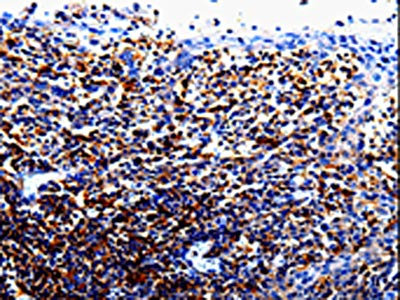

圖片:

應用范圍:ELISA,IHC

Application Recommended Dilution ELISA 1:1000-1:5000 IHC 1:50-1:200 -

組織特異性:Primarily expressed in hematopoetic cells including B-cells, T-cells, NK cells, monocytes and macrophages. Not expressed in non-hematopoetic cells such as fibroblasts or endothelial cells.